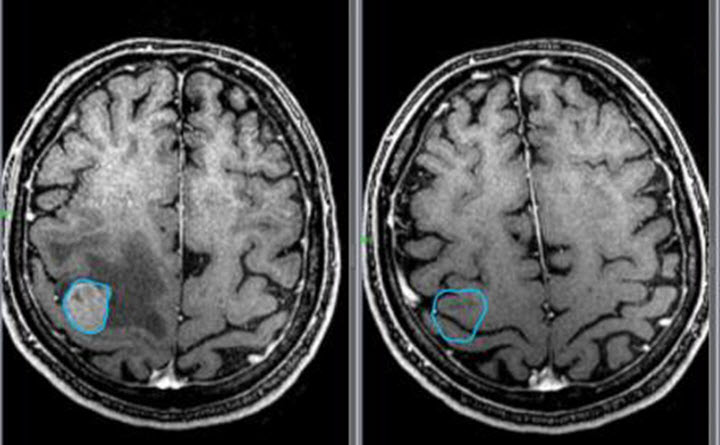

В неясных ситуациях применяется МРТ (магнитно-резонансная томография). В отличие от КТ (компьютерной томографии) метод не несет лучевой рентгеновской нагрузки и может быть применен даже в III триместре беременности. Но из-за технической сложности у грудных (и до 6 – 7 лет) детей способ выполняется только под наркозом и имеет ряд противопоказаний. Данная процедура входит в план обследования при подготовке к хирургическому лечению.

УЗИ головного мозга информативно только на первом году жизни ребенка, до зарастания родничка (подробнее в статье: когда и как зарастает темечко у ребенка?). Его назначают недоношенным детям, а также перенесшим кислородное голодание и тяжелые роды. Детям старше одного года и взрослым проводят МРТ. Эти методы дифференцируют кисту и псевдокисту.

В случае выявления образования невропатолог назначает пациенту повторное обследование, для того чтобы определить растет оно или нет. Если ко второму визиту к врачу киста осталась прежних размеров или увеличилась, младенцу назначается терапия, которая призвана предотвратить появления головной боли и судорог. В старшем возрасте псевдокиста исследуется при помощи МРТ и КТ. Благодаря этим исследованиям удается удостовериться в отсутствии опухоли.